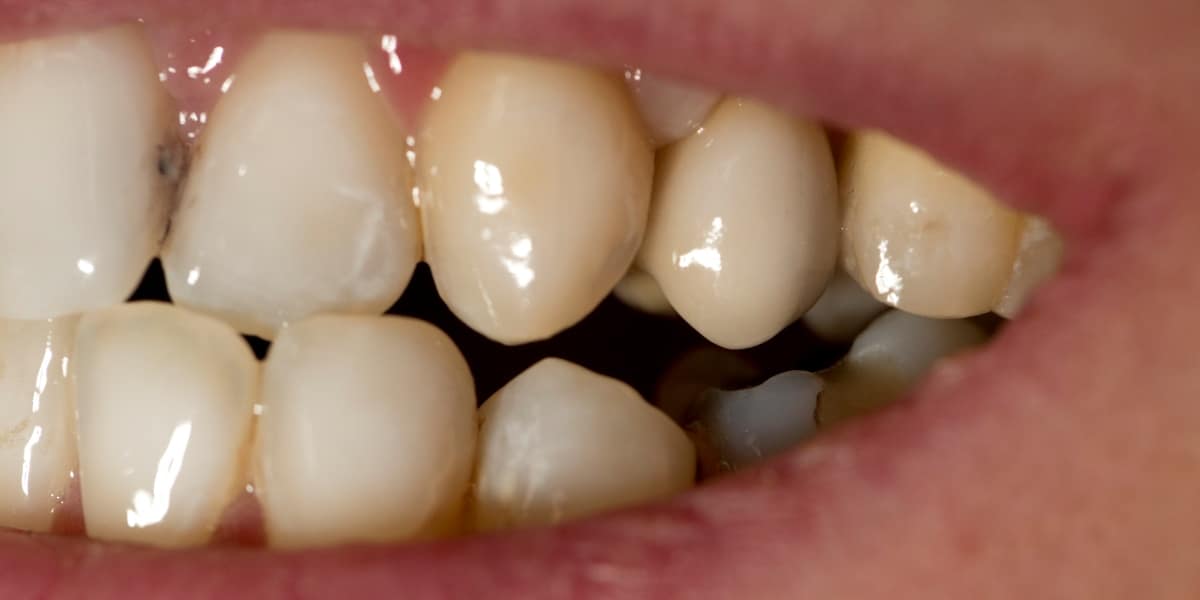

Zubní implantát je alternativním protetickým řešením, neboť chybějící zuby lze kromě klasického můstku klinicky vhodněji nahradit zubním implantátem, který splňuje všechny funkce původního zubu a navíc je jeho přirozenou a věrnou kopií, bez nutnosti zbrousit (degradovat) jiné okolní zuby (jako v případě můstku).